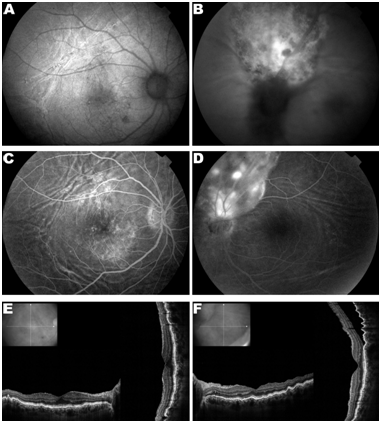

Sixty-six years old female presents complaining of decreased unilateral visual acuity on her left eye. Medical and family history had no relevant data. The ophthalmologic examination revealed visual acuity of 20/40 in the right eye (OD) and 20/100 in the left eye (OS). The slit lamp examination showed no change in both eyes (OU) and the intraocular pressure was 14mmHg in OU. The fundus examination showed choroidal folds and drusen in the posterior pole of the OD (Figure 1A) and elevated hypo chromic lesion on the upper edge of the optic disc and choroid (Figure 1B). Complementary imaging examinations were performed: Fundus autofluorescence (FAF) (Figure 2A) (Figure 2B) fluorescein angiography (FA) (Figure 2C) (Figure 2D) and optical coherence tomography (OCT) (Figure 2E) (Figure 2F). Ultrasonography (USG) was performed on the left eye revealed intraocular tumor measuring 4.80mm x 12.93mm x 13.58mm (HxLxT). The patient was referred for oncology evaluation. There were performed X-ray of the chest and full abdomen and a magnetic resonance imaging (MRI) of the chest. MRI revealed a tumor in the lower lobe of the right lung. Tumor excision followed by biopsy characterized as adenocarcinoma.

Figure 2 Complementary imaging examinations. (A) Fundus auto fluorescence (FAF) of the right eye (OD) highlighting choroidal folds and macular retinal pigment epithelium (RPE) changes. (B) FAF of the left eye (OS) presenting hiper and hipo autofluorescent areas in tumor surface. (C) OD fluorescein angiography (FAG) showing hyperfluorescence by window defect in the macular area and highlighting choroidal choroidal. (D) End stage of OS FAG presenting hiper and hipo fluoerescentare as at the tumor. (E) OD optical coherence tomography (OCT) showing in creasedtortuosity of the row for EPR dueto choroidal folds. (F) OS OCT shows serous retinal detachment superior and involving part of the macula. Choroidal folds can be seen especially in the upper and temporal areas.